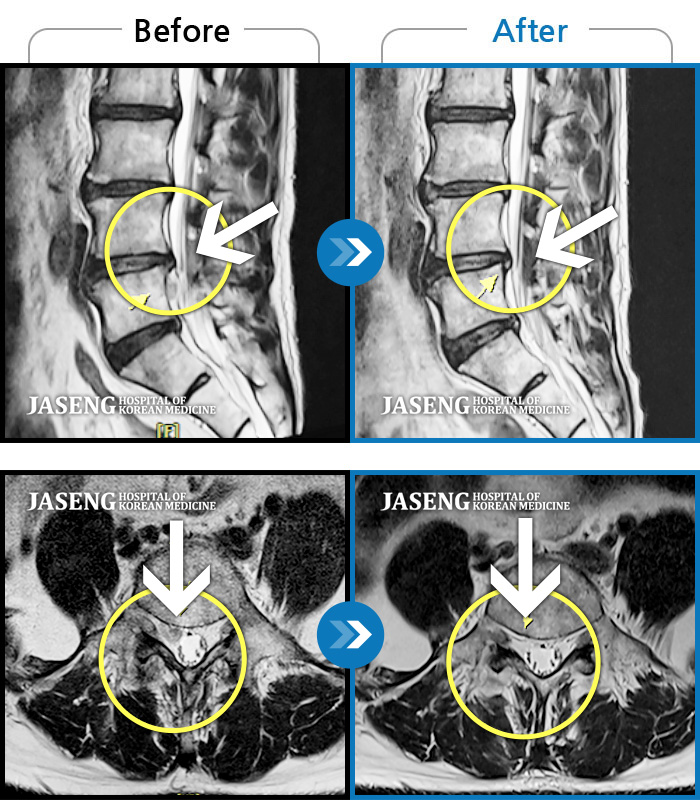

Before

After

허리 양측 둔부에서 발가락으로 통증, 비증, 힘이 빠지는 증상

2018.08.11 ~ 2019.03.27